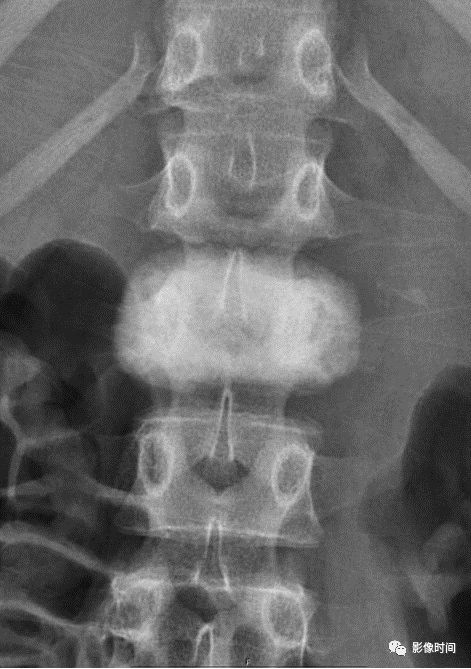

10栅栏征

栅栏征(The Palisade sign),也称灯芯绒椎体(corduroy vertebra)或灯芯绒征(corduroy sign)

脊椎椎体因病变导致骨小梁吸收、稀疏,为满足承重需要,存留的纵向骨小梁粗大;粗大骨小梁间以细条状密度减低区,形成栅栏样影像,故称栅栏征或灯芯绒椎体。

栅栏征最常见于血管瘤,以单个脊椎居多;骨质疏松如泛发性骨质增生症、老年性骨质疏松等亦可呈现此类表现,一般见于下胸椎、上部腰椎的多个椎体,只是伴有普遍的骨密度减低。有时自颈椎至腰椎全部椎体均出现栅栏征。栅栏征主要见于椎体。

典型病例

病例 1,脊柱血管瘤。胸腰椎 CT 冠状位、矢状位 MPR 重建示胸 12 椎体松质骨密度降低,其中可见粗大骨小梁呈栅栏状。

病例 2,67 岁女性,椎体血管瘤。腰椎侧位片示胸 12 及腰 3 椎体呈现栅栏征,磁共振检查证实为血管瘤。